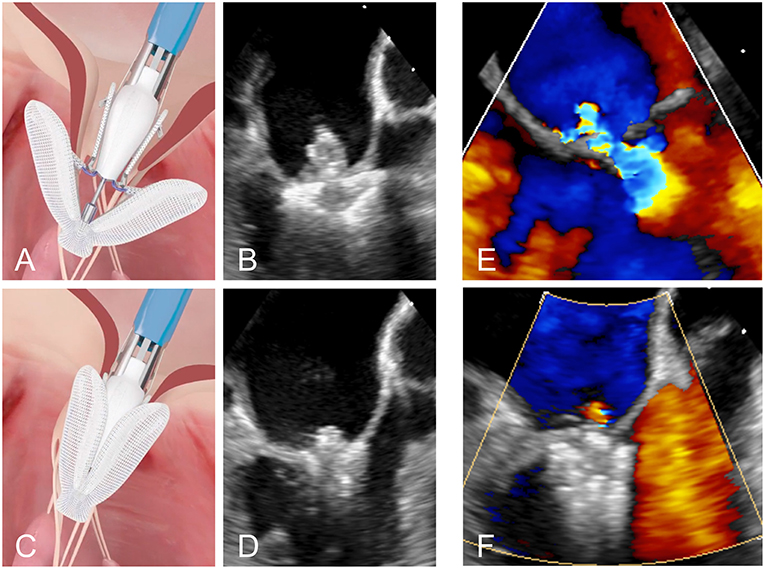

The Edwards PASCAL Transcatheter Valve Repair System has been designed to address some of the limitations of previous systems. It is intended to reduce the tension on the valve leaflets by introducing a 10 mm central spacer within the MV regurgitant orifice. The paddles of the implant are also wider and curved to further reduce tension and the system allows for independent grasping of the leaflets. This may be particularly useful in the presence of a large prolapse gap (Figure 4) or in patients with retraction or tethering of the posterior leaflet. The device is also designed to be easier navigated in the left atrium and offers a higher degree of steerability. A first-in-human feasibility experience of the device has been described from a series of 23 compassionate use cases (17). These early data were encouraging with MR ≤2+ in 97% of the patients at discharge and without elevated gradients despite a larger device size.

Figure 4. (A,B) Positioning of the PASCAL device in the mitral valve. (C,D) Grasping of the two leaflets. (E,F) Transoesophageal Doppler image of a case of severe MR before and after leaflet repair with the PASCAL device, respectively.